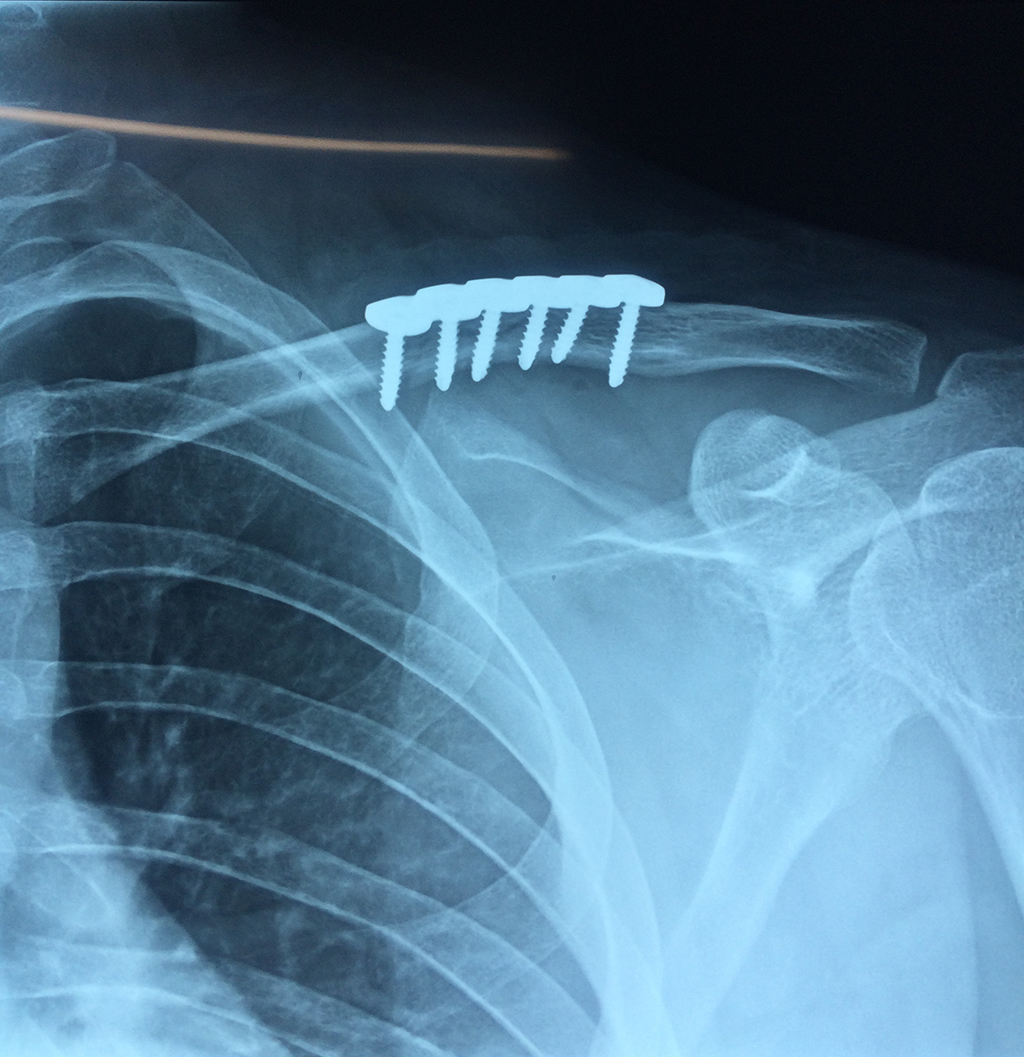

Fémur - Clavícula

La clavícula es un hueso largo, con forma de "S" itálica, situado en la parte anterosuperior del tórax. Junto con la escápula forman la cintura escapular. Se puede palpar por toda su longitud y se extiende del esternón al acromion de la escápula, siguiendo una dirección oblicua lateral y posterior.